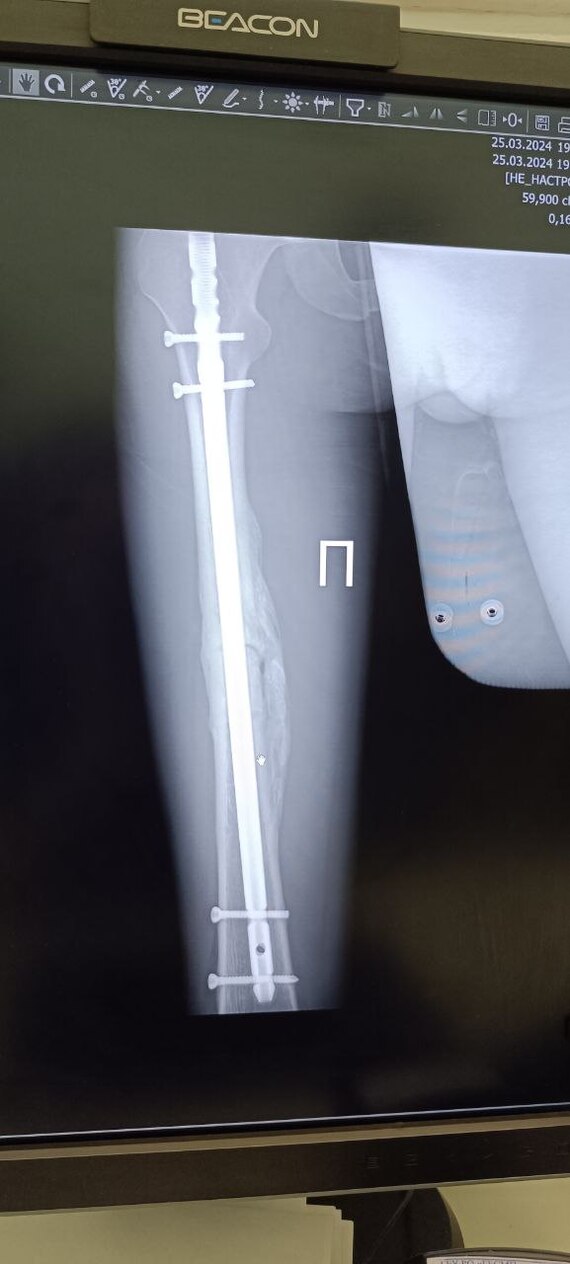

Я двигаясь по улице Сальский переулок в сторону улицы Вятской на зеленый сигнал светофора, влетев в автомобиль перелетел его, пробив головой стекло. Благодаря очевидцам которые во время оказали помощь и вызвали скорую, я остался жив, в то время как предполагаемая виновник аварии вышла из машины, ушла и начала кому то звонить. В последствии я провел в реанимации 7 дней, получил 7 переломов тела как закрытых так и открытых, разрыв тканей и сотрясение головного мозга и перенес множество операций и еще предстоит одна операция в августе этого года.

Мне 24 года у меня большие проблемы со здоровьем, в этом году ждёт вновь операция , ни извинений, ни помощи, где справедливость?! Пока другая будет отсиживаться и ждать закрытия дела как и полиция, я должен будучи больным содержать семью, бегать по больницам и пытаться. решить проблемы которые я себе же не создавал.